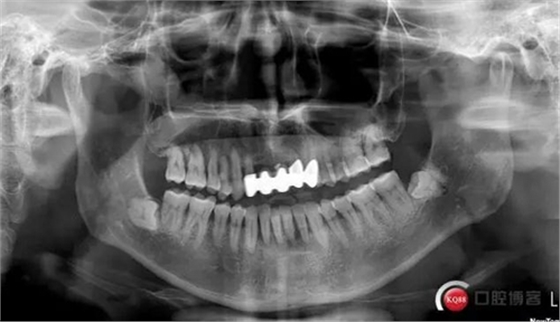

此患者為下頜前牙區(qū)松動(dòng)牙試保留案例,牙周炎伴根尖周炎,并且31頰舌雙根管。術(shù)中由于我的個(gè)人失誤,導(dǎo)致整體治療過(guò)程延長(zhǎng),特此總結(jié),自我警醒。

患者蔣某,男性,1963年出生。2017年7月4日就診。

主訴:下前牙松動(dòng)約三年

現(xiàn)病史:患者約三年前發(fā)覺(jué)下頜前牙開始松動(dòng),伴加重,現(xiàn)影響咬合。曾于外院就診,行牙周潔治(約一年前),建議拔除下頜前牙后種植,患者拒絕。

檢查:口腔衛(wèi)生狀況欠佳,牙面可見大量色素附著,牙石II°,尤以下頜前牙舌側(cè)及后牙頰側(cè)為重。牙齦紅腫,BI3-4°,PD下頜前牙區(qū)4-6mm。31松動(dòng)III°,溫度測(cè)試無(wú)反應(yīng),叩不適。32、41、42松II°+,32溫度測(cè)試遲鈍,叩(-)。

X線示牙槽骨吸收,下頜前牙區(qū)可見齦下牙石影像,牙槽骨吸收至根尖1/3,根周透射影像。

診斷:慢性牙周炎

31慢性根尖周炎

32牙髓充血?慢性牙髓炎?